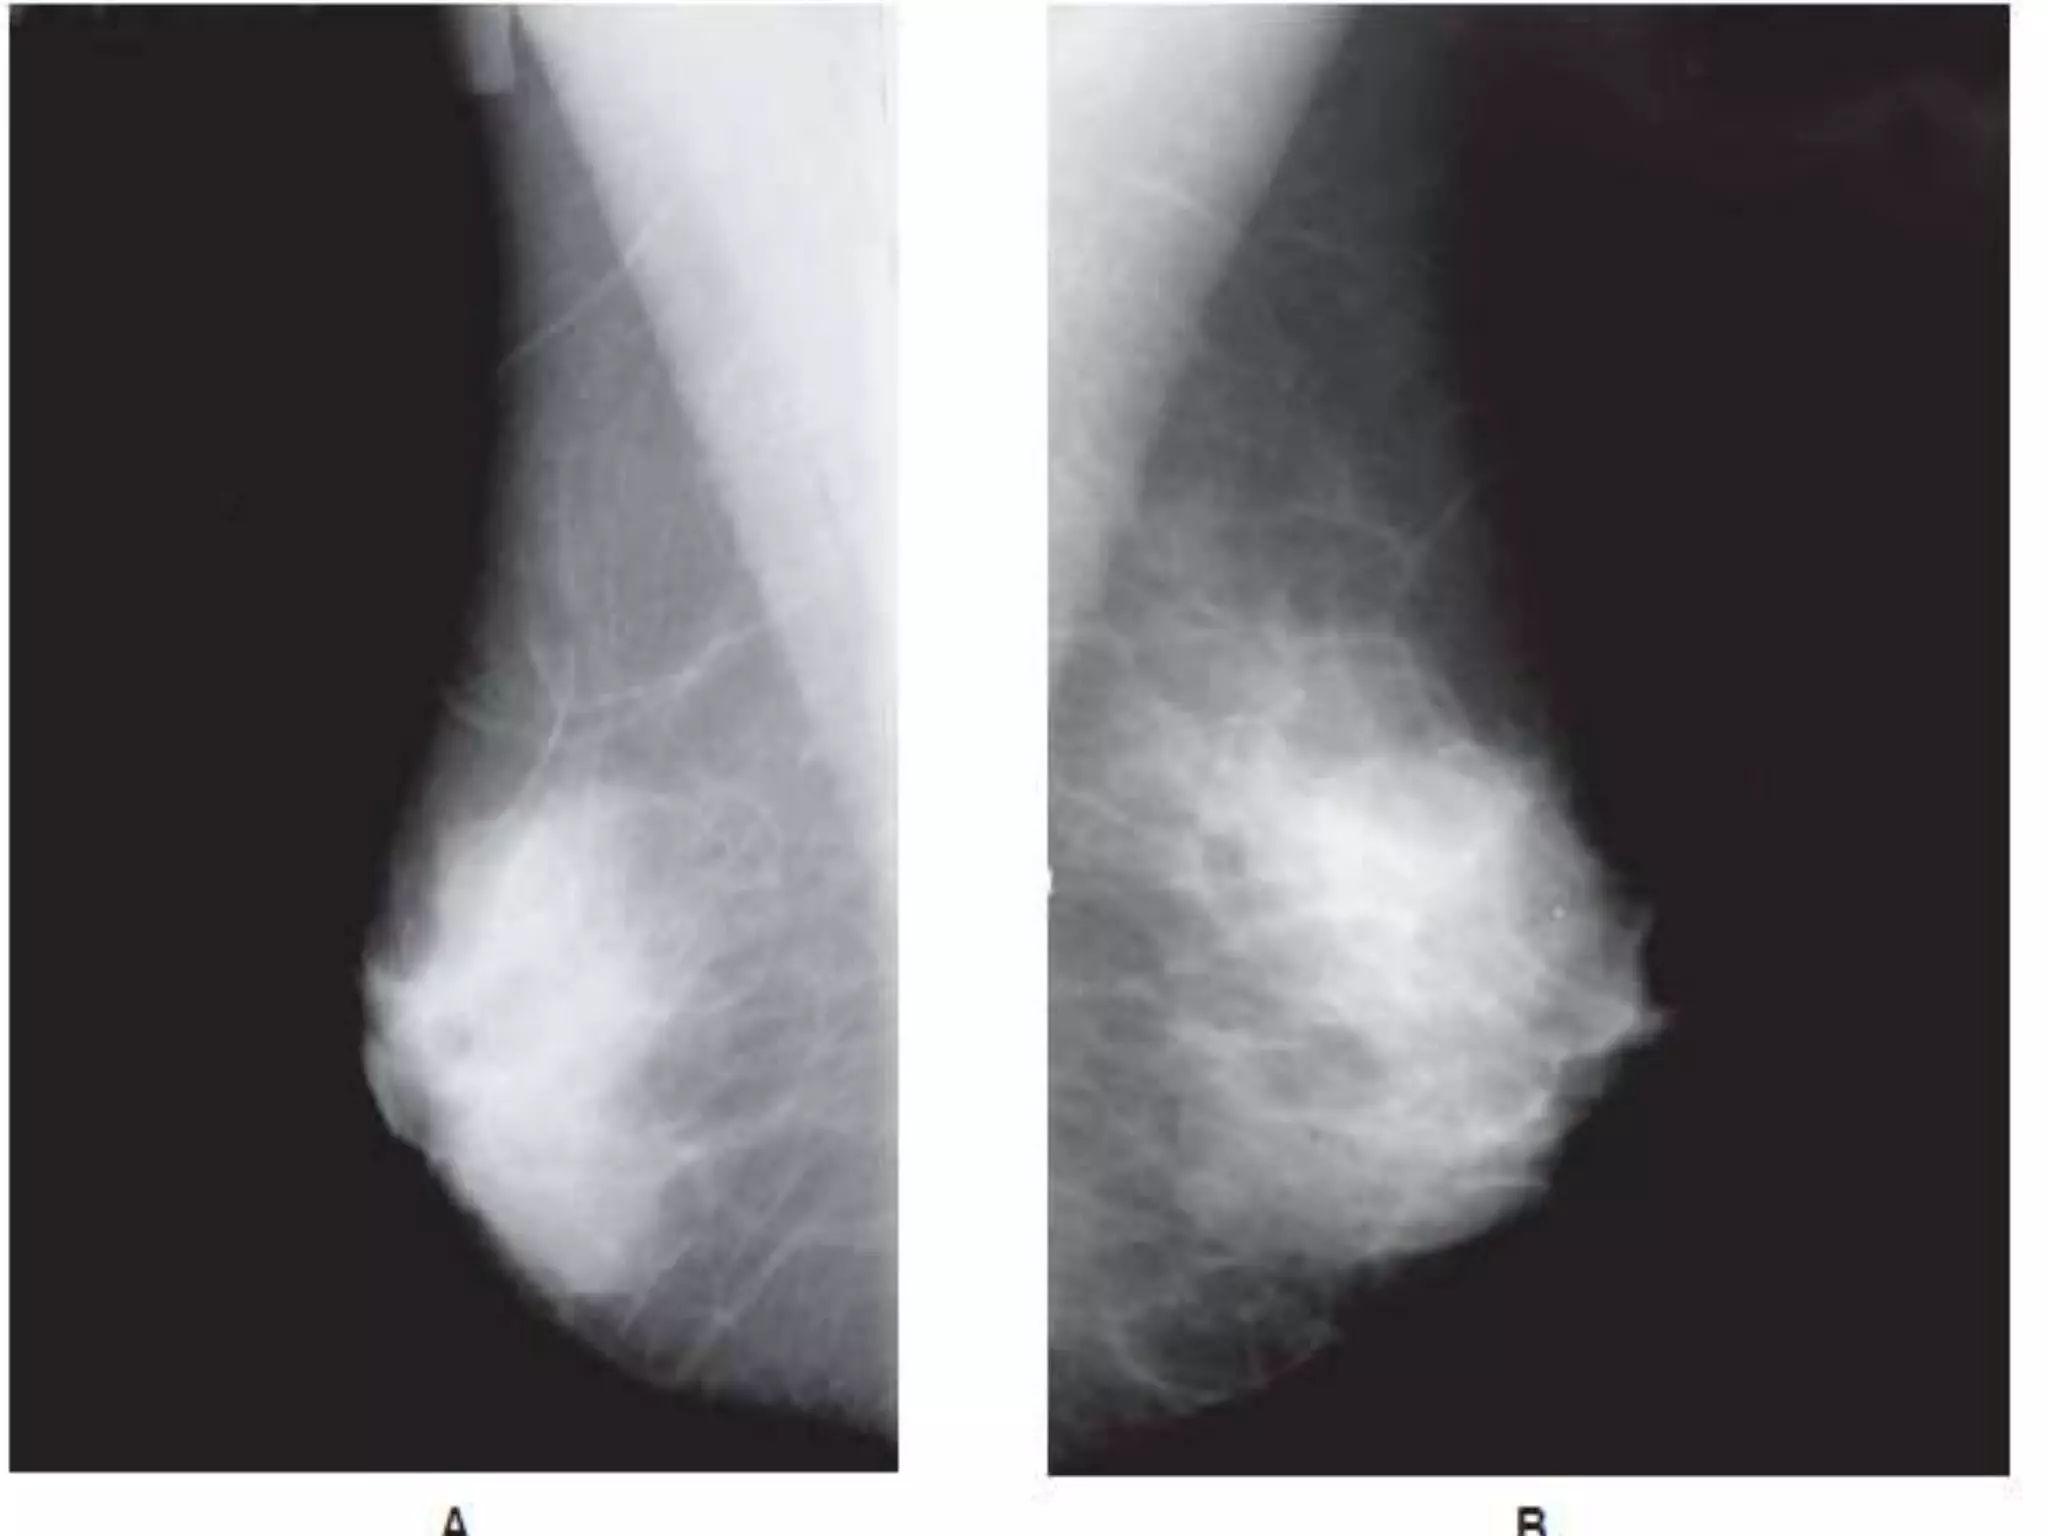

MEDIOLATERAL OBLIQUE VIEW

 Best view to image all of the breast

tissue and the pectoral muscle .

 The C-arm of the mammographic

unit is rotated to 45 degree so that

the cassette is parallel to the

pectoral muscle .

 The film holder is kept high up in the

axillary fossa and the patient s arm

is abducted at the elbow by

80degrees.

 The xray beam enters the breast

from the medial side –compression

is applied to the pectoralis major

muscle .